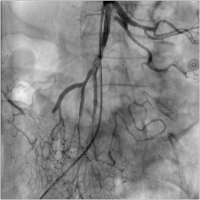

Abbildung 1: Kontrasmittel NTCT mit Verschluss der A. mesenterica superior

Keywords:

Angiologie

,

Gefäßmedizin